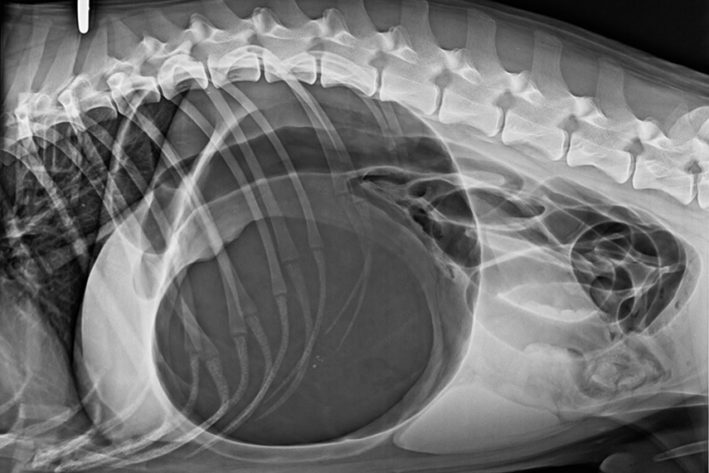

Röntgen Magendrehung beim Hund: hochgradig aufgegaster und gedrehter Magen.

Häufige chirurgische Eingriffe finden in der Bauchhöhle wegen Tumoren oder Fremdkörper im Magen-Darmtrakt statt. Enterotomien (Eröffnung des Darms) oder gar Darmresektionen (Teilentfernung eines Darmabschnittes) werden hierbei durchgeführt. Auch die Entfernung der Milz aufgrund eines rupturierten Milztumors stellt eine häufige Indikation für die Eröffnung der Bauchhöhle dar. Bei Fällen in denen mittels Bildgebung (Röntgen, Ultraschall, CT, …) keine Diagnose gestellt werden kann und dennoch die Abklärung wichtig ist, kann eine Laparotomie mit Inspektion und Beprobung verdächtiger Bauchorgane Gewissheit bringen.